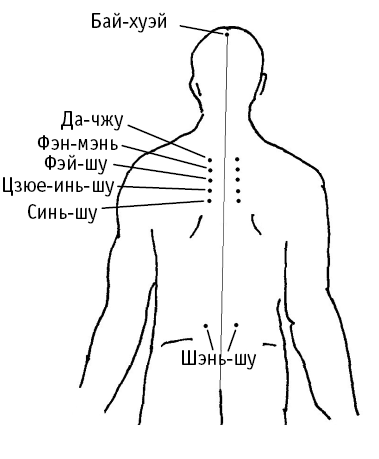

Бай-хуэй («соединение пересечений») расположена в центре темени, на пересечении срединной линии головы с линией, соединяющей кончики ушей.

Да-чжу («большой челнок ткацкого станка») расположена под остистым отростком 1-го грудного позвонка с двух сторон (на 1,5 цуня по горизонтали от середины спины).

Фэн-мэнь («ворота ветра») расположена под остистым отростком 2-го грудного позвонка с двух сторон на 1,5 цуня по горизонтали от середины спины.

Фэй-шу («точка спины легких») расположена под остистым отростком 3-го грудного позвонка с двух сторон на 1,5 цуня по горизонтали от середины спины.

Цзюе-инь-шу (в восточной медицине она считается главной ТОЧКОЙ СПИНЫ ПЕРИКАРДА, то есть оболочки сердца). Расположена под остистым отростком 4-го грудного позвонка с двух сторон на 1,5 цуня по горизонтали от середины спины.

Синь-шу считается ТОЧКОЙ СПИНЫ И СЕРДЦА. Она находится под остистым отростком 5-го грудного позвонка от середины спины с двух сторон на 1,5 цуня по горизонтали от середины спины.

Шэнь-шу («почка, точки спины») расположена на 1,5 цуня кнаружи от остистого отростка 2?го поясничного позвонка, «на поясе» с двух сторон. Воздействуя на нее, можно достичь дополнительного лечебного эффекта, если пациент страдает: недержанием мочи или частым мочеиспусканием; импотенцией; головокружением, головной болью, шумом в ушах; болями в спине, а также коленях.